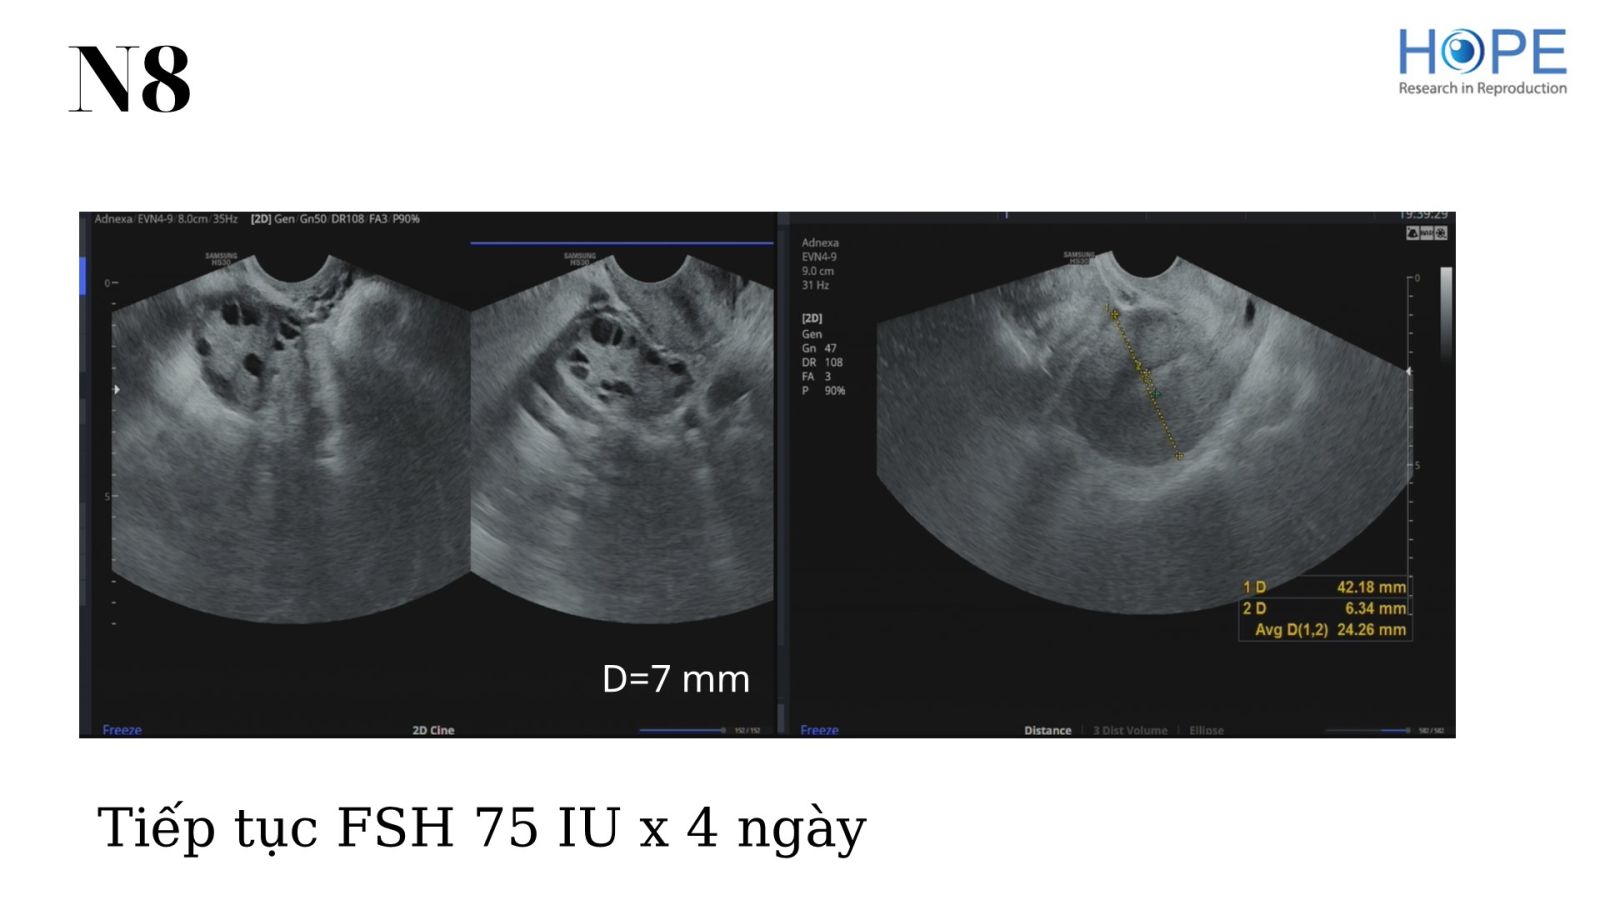

Các phác đồ kích thích buồng trứng nhẹ để IUI –  cách theo dõi kích thích buồng trứng

BS Lê Thị Hà Xuyên - IVFMD Phú Nhuận